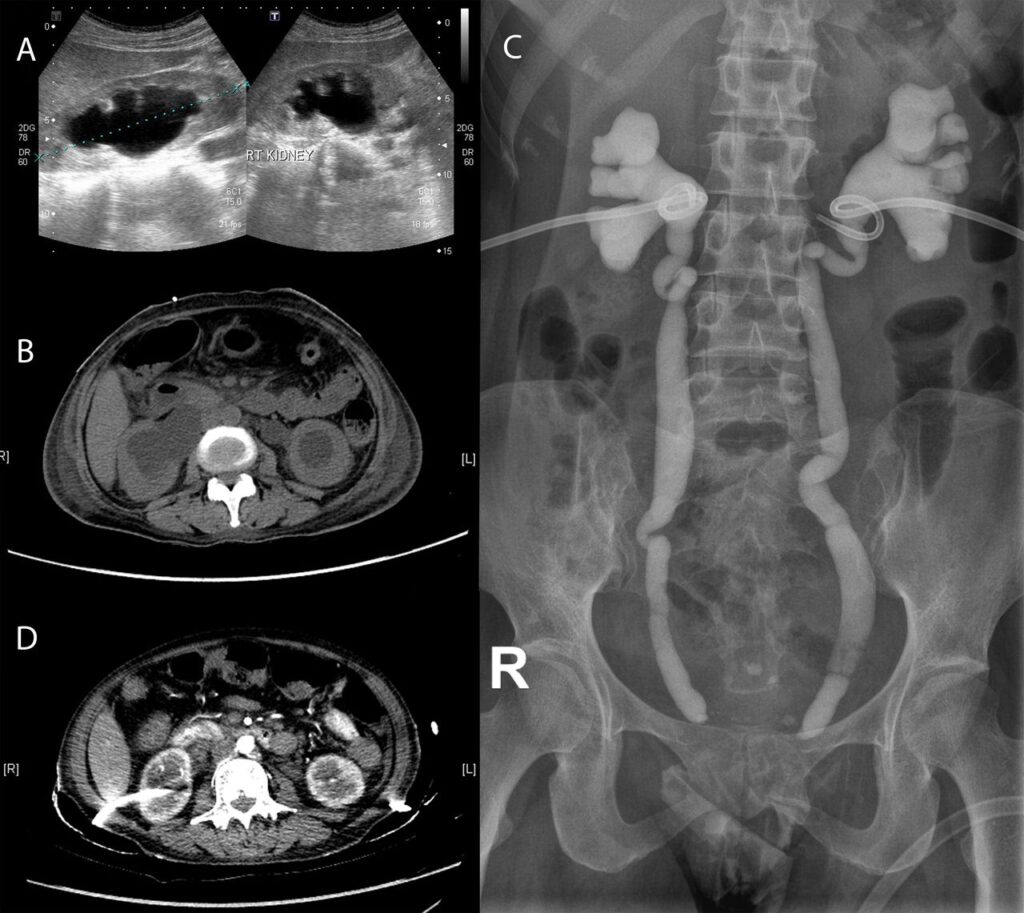

- CT-scanning og ultralydsscanning: Disse undersøgelser er centrale i diagnostikken. De kan afsløre en karakteristisk fortykket blærevæg, nedsat blærekapacitet og, vigtigst af alt, tegn på komplikationer som hydroureter (udvidet urinleder) og hydronefrose (vand i nyrerne). Hydronefrose opstår, når urinen ikke kan passere frit fra nyrerne til blæren på grund af hævelse og fibrose ved urinledernes indmunding i blæren.

Den mest alvorlige konsekvens af forsinket diagnose og behandling er udviklingen af hydronefrose. Hvis urinen stuver op i nyrerne over længere tid, kan det føre til permanent og irreversibelt nyresvigt.